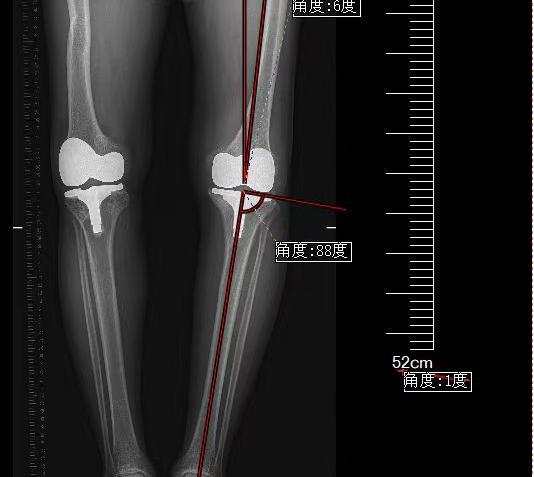

患者在省内辗转多家医院,得知王伟教授在洛阳市中心医院骨科工作,相信困难会被解决。王伟教授率领骨科关节团队,仔细分析病情,观测炎症指标,并邀请西交大二附院骨科全国骨科顶级专家,中华医学会骨科分会候任主任委员王坤正教授团队远程会诊,做出最终研判:患者并非关节感染,是由于左下肢长了4厘米,长期关节不平衡,造成患者左膝关节机械性松动。如何翻修手术,刘营杰主任提前精细测量患者下肢畸形角度、下肢长度,做出术前规划,提前定制矫形鞋,纠正下肢不等长。王伟教授、王伟民主任制定术前预案,一期做了左膝关节翻修手术,术后证实,患者诊断完全符合术前判断。经过两周的精心护理,患者顺利出院。术后1个月复查,患者已完全脱离了拐杖,恢复了正常生活。患者从10万余元的预算到最终花费5万余元,为患者减轻了经济负担,精准的诊断为患者缩短了治疗时间。